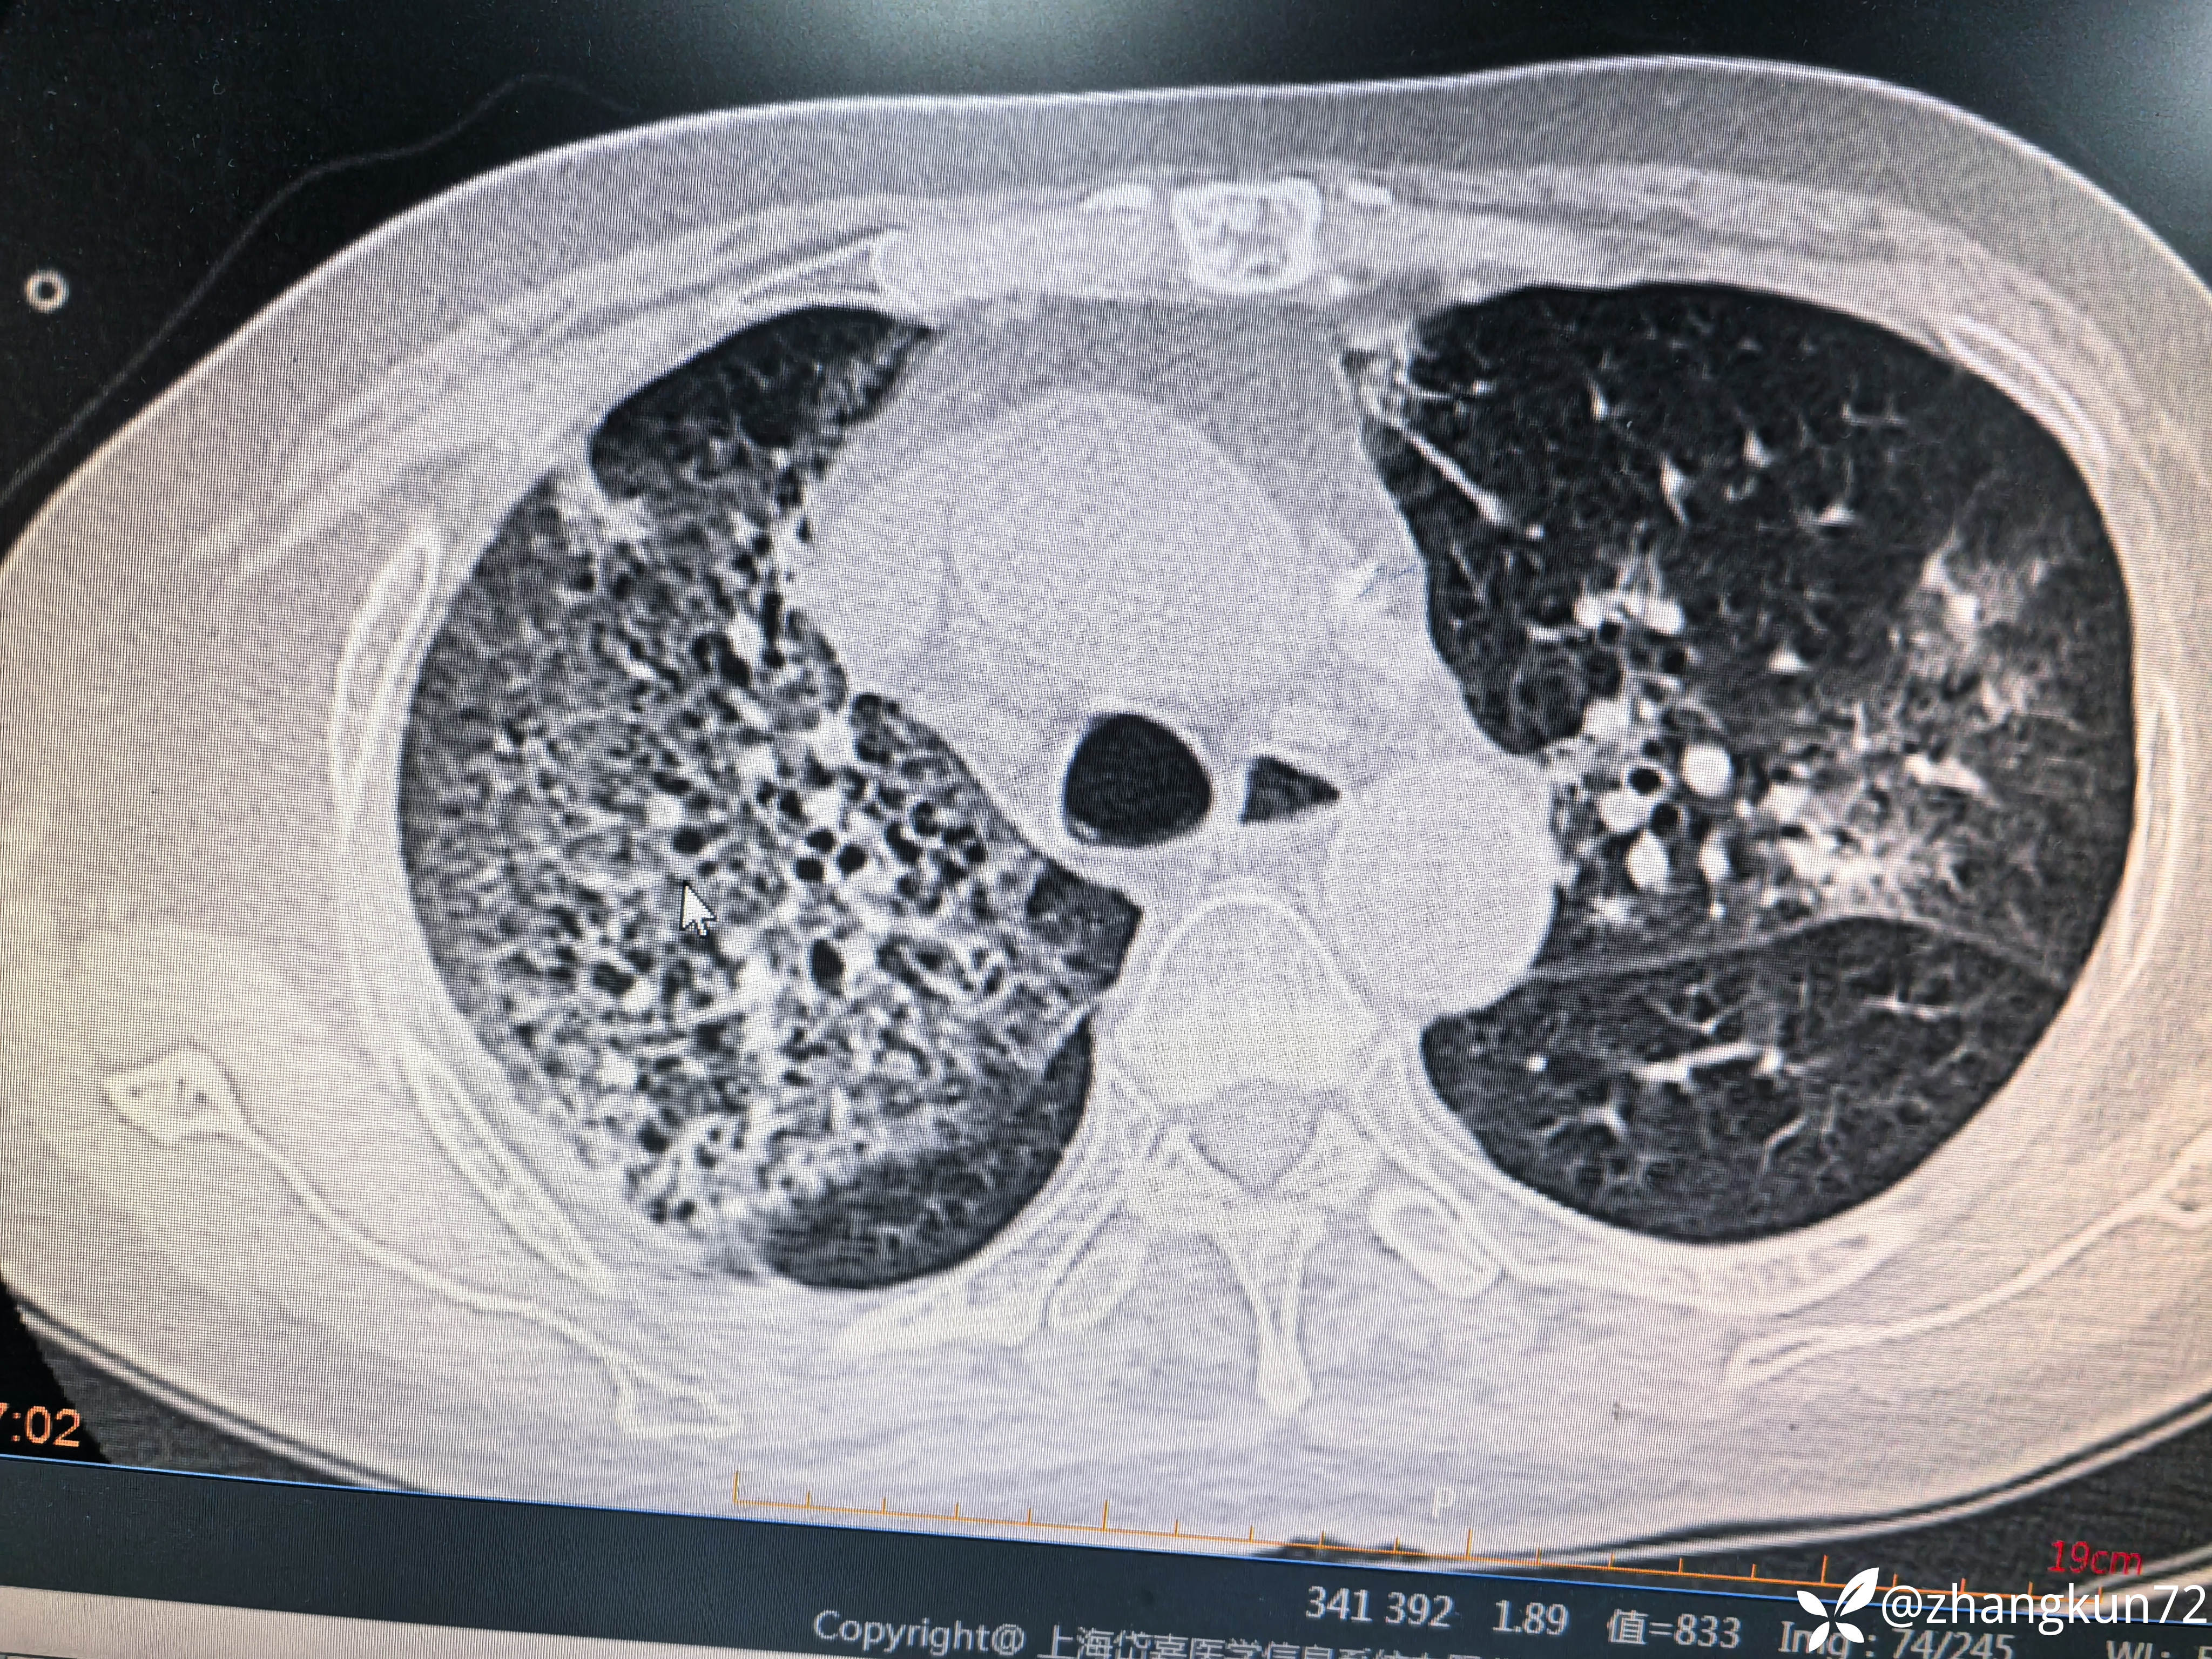

异常胸部ct

【检查】:白细胞计数正常,超敏c反应蛋白6.41,降钙素原0.09,白介素6 9.04,真菌G试验阴性,GM试验1.13,新冠核酸阴性,甲流阴性,乙流阴性,支原体抗体阴性,梅毒及艾滋病等病原体阴性,痰培养一次检查肺炎克雷伯杆菌。

【临床诊断】:1型呼吸衰竭,肺部感染,肾上腺皮质功能减退证,甲状腺功能减退症

【治疗经过及结果】:予口服左甲状腺素片,静脉注射氢化可的松,亚胺培南联合莫西沙星抗感染

目前治疗一般,是否为感染,什么病原体感染